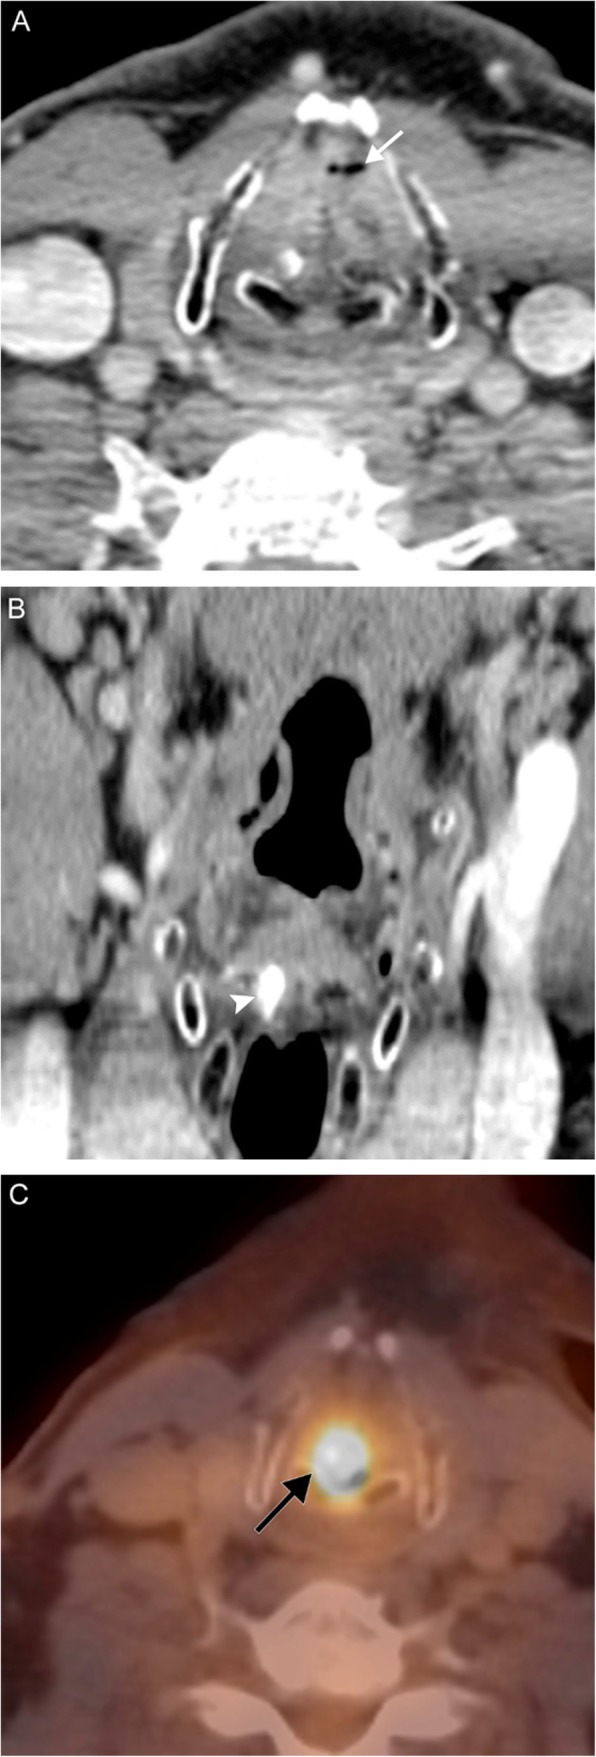

Fig. 6.

Laryngeal carcinoma. A 59-year-old man with 45-pack-year smoking history presenting with 6 weeks of hoarseness. Axial (a) and coronal (b) contrast-enhanced CT images reveal near-complete obliteration of the laryngeal airway by a polypoid soft tissue mass, which extends inferiorly into the subglottic airway. Note the trace residual airway remnant anteriorly (white arrow). There is asymmetric high attenuation of the right arytenoid cartilage (white arrowhead), consistent with sclerosis and involvement of the lesion. Axial fusion PET/CT image (c) reveals a hypermetabolic mass centered at the larynx (black arrow). Biopsy revealed squamous cell carcinoma